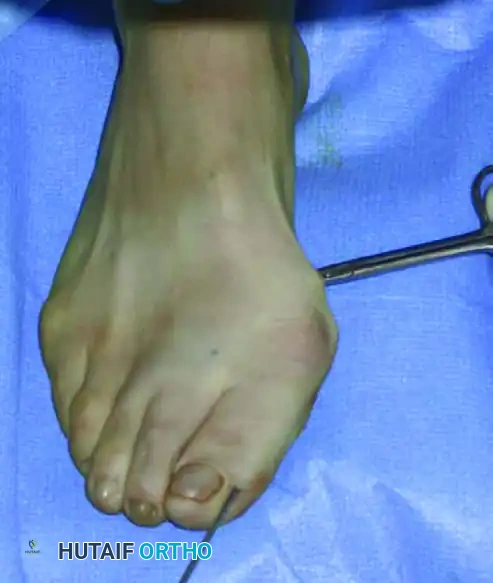

يتم تأكيد الشكل النهائي للقدم وموقع السلك المعدني باستخدام الأشعة السينية. يعتبر التصحيح ناجحا عندما تكون العظام مصطفة بشكل مستقيم وسليم.

التأكيد النهائي لشكل القدم بالأشعة

في النهاية، يتم قص الجزء الزائد من السلك المعدني خارج الجلد وثنيه، ويتم إغلاق الشق الجراحي الدقيق بغرزة واحدة أو أشرطة لاصقة معقمة.

الأيام الأولى بعد الجراحة

مباشرة بعد العملية، يقوم الفريق الطبي بوضع ضمادة ضاغطة متخصصة. يتم تثبيت إصبع القدم الأكبر في وضعية مصححة بدقة باستخدام أشرطة لاصقة طبية. يجب عدم العبث بهذه الضمادة أو تغييرها إلا بواسطة الطبيب المعالج خلال الأسابيع الأربعة الأولى.